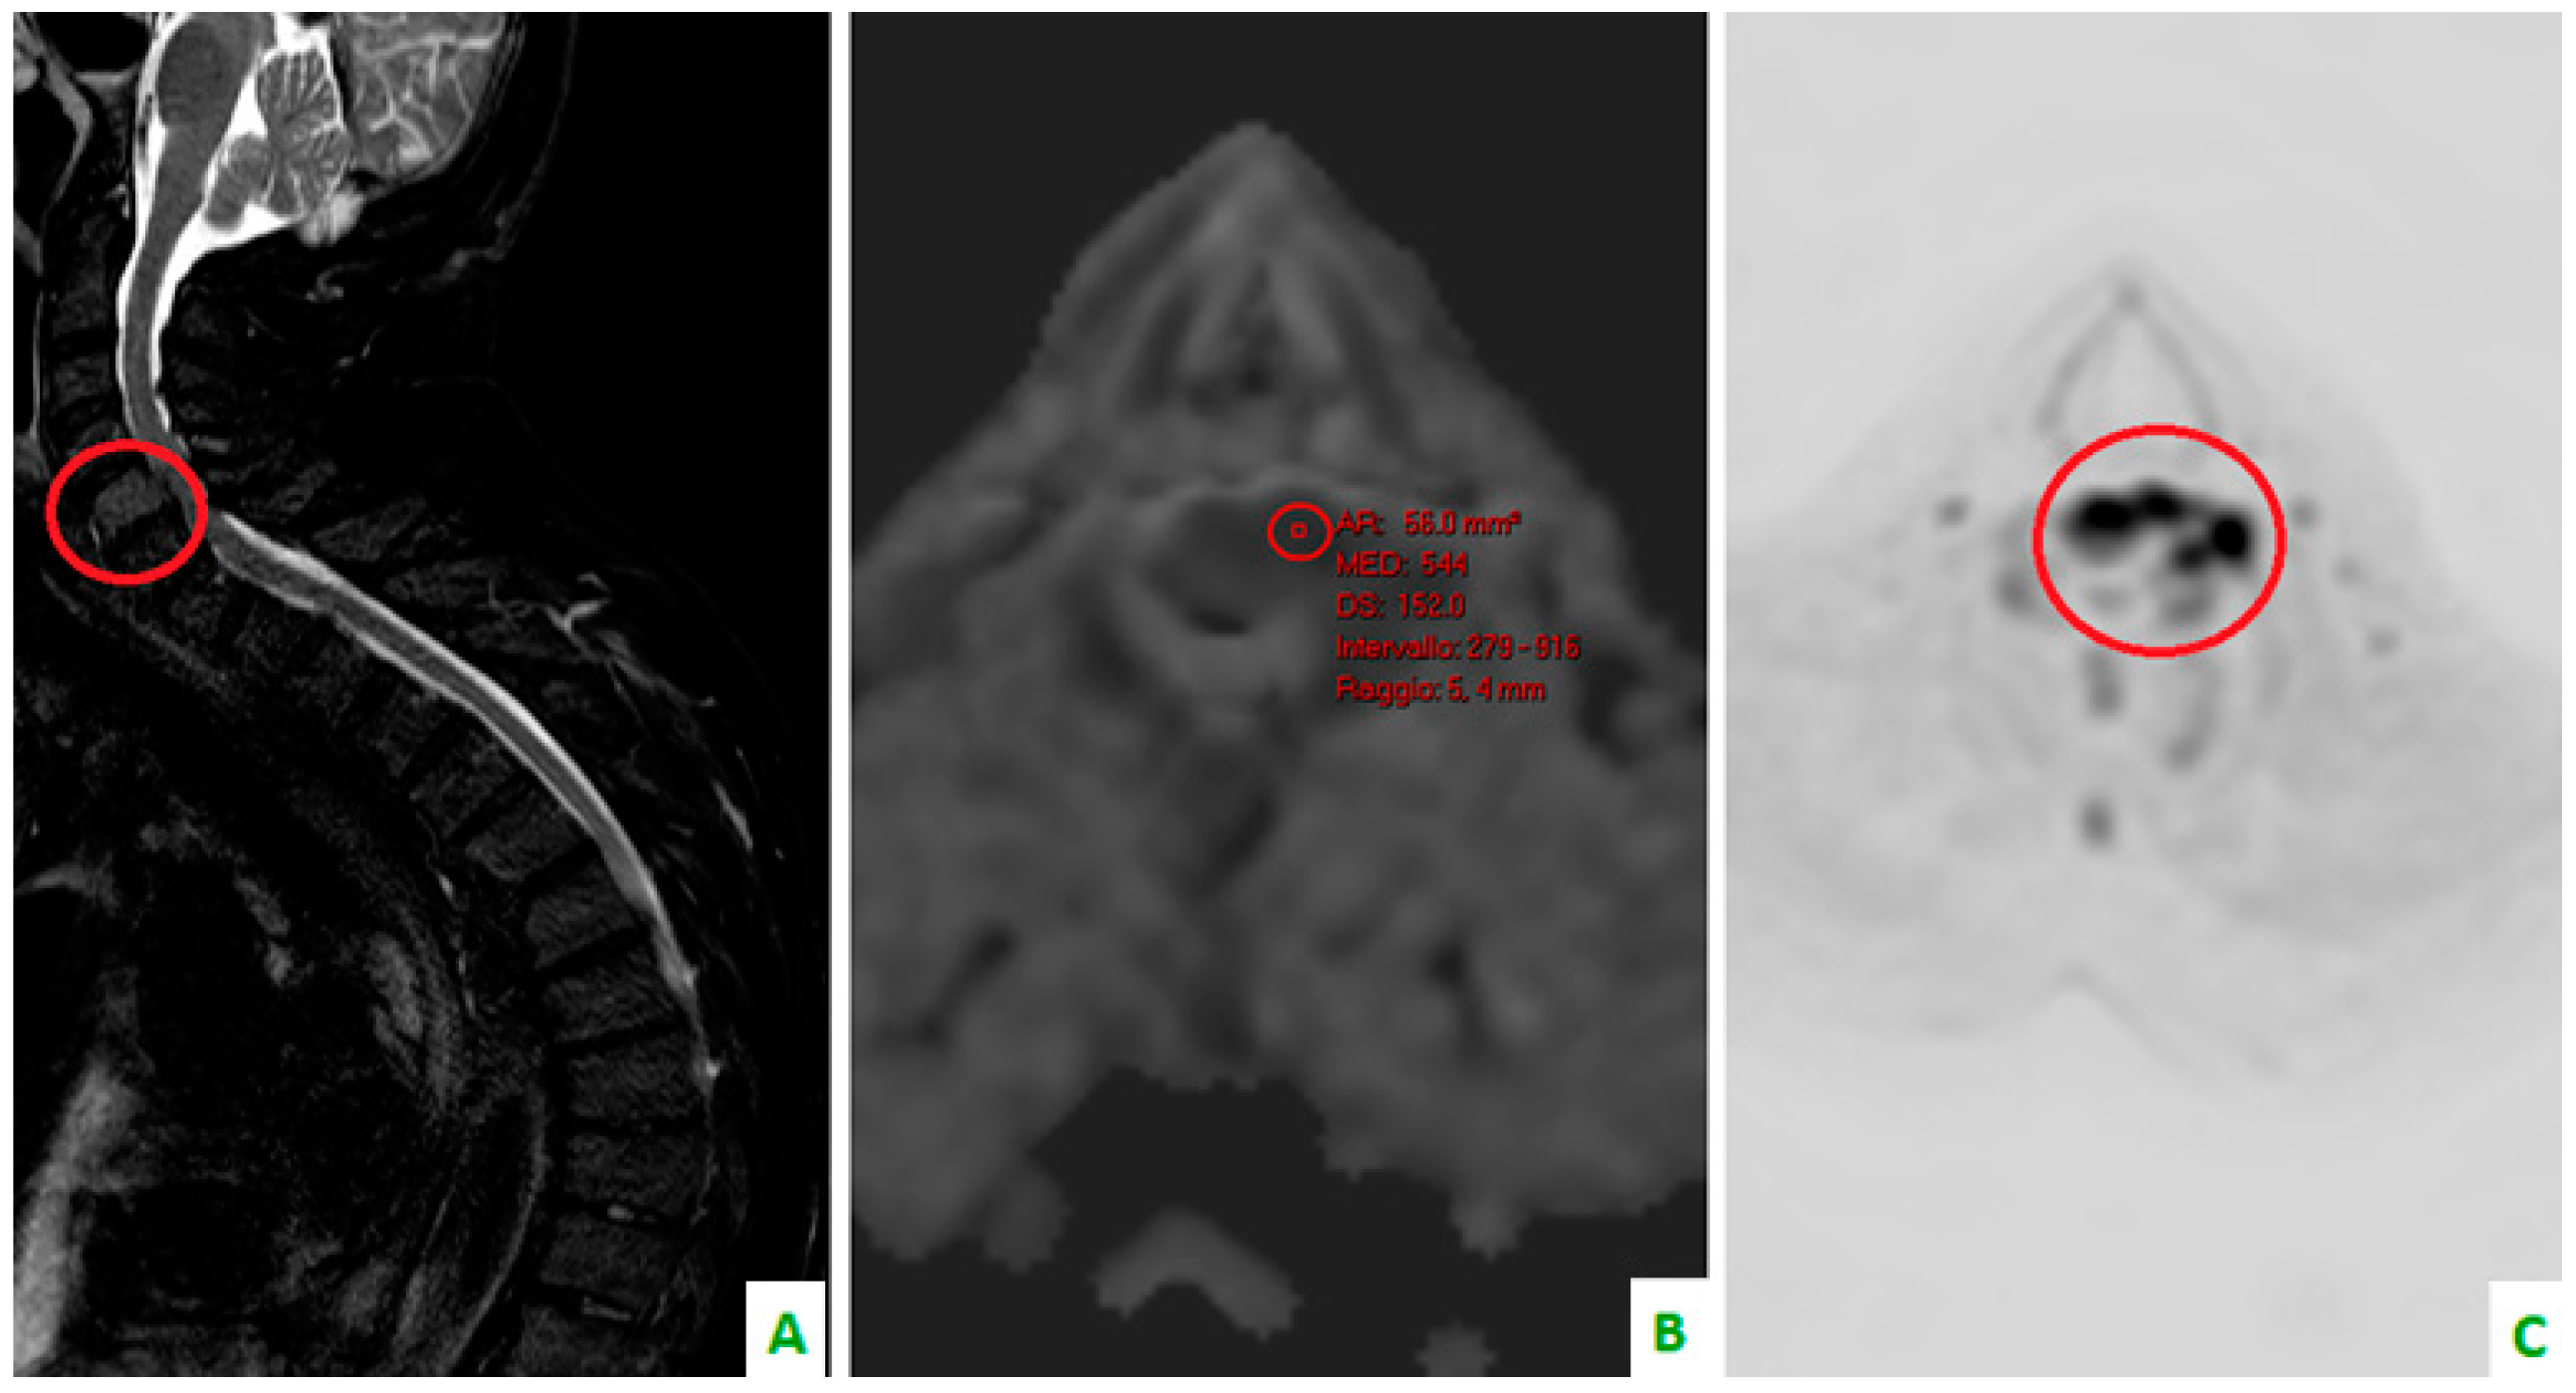

Figure 5. (A) A T1 sequence and (B) STIR sequence, performed with a dedicated spinal MRI, highlight the lung metastases. (C) Cervical spine on a sagittal reconstruction of a computed tomography (CT). The bone metastasis is not so clear.

Skeletal metastases, which are predominantly osteolytic, localize in the spine in 50% of patients. This the most common area of localization, followed by the ribs (27.1%), ilium (10%), sacrum (7.1%), femur (5.7%), and the humerus, scapula, and sternum (2.9%). This is according to a retrospective study by Tsuya et al. [27] (Figure 3, Figure 4 and Figure 5).